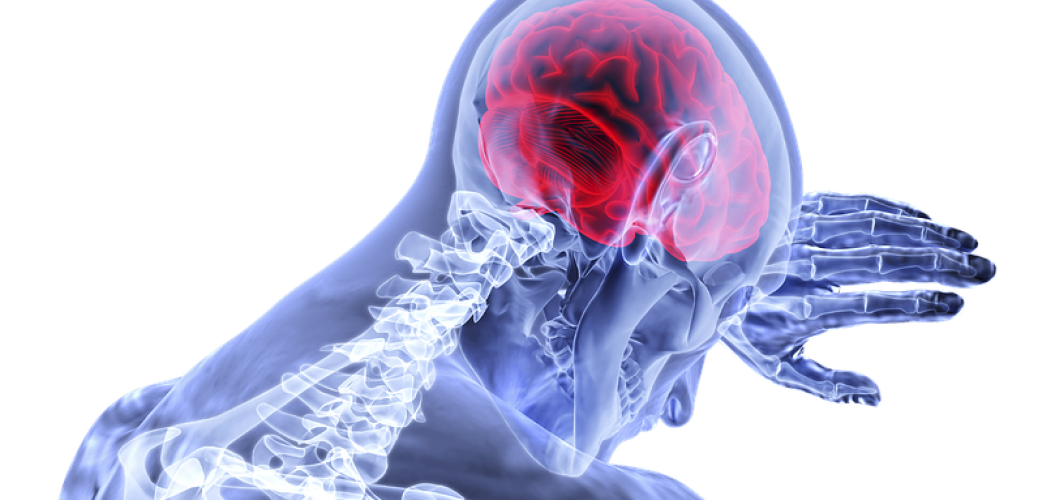

醫管局最新一期《風險通報》列出去年第4季18宗醫療風險警示事件和重要風險事件,有醫護人員因認為病人家屬能即日將病人所需的抗凝血藥帶入院,未有向病人提供有關藥物,病人漏服一次藥後,翌日左邊身乏力,檢查證實腦梗塞。有藥劑師稱,暫停服用有關藥物可增加中風風險。

當中一名因頭暈入院的陣發性心房顫動病人,本身需每日服兩次抗凝血藥Apixaban,但醫護人員獲悉其家屬可帶藥物入院給病人後,假設家屬可即晚帶入院,當晚無向病人提供Apixaban,病人翌日開始左邊身乏力,電腦掃描檢查發現病人腦梗塞。

香港醫院藥劑師學會會長崔俊明稱,Apixaban是新一代抗凝血藥,心房顫動病人服此藥以預防中風,漏用藥可增血管栓塞風險,因此病人一定不能自行停藥,外國就曾報告有病人停藥後中風。至於今次個案漏服一次藥與腦梗塞是否有關係,崔俊明說需調查。